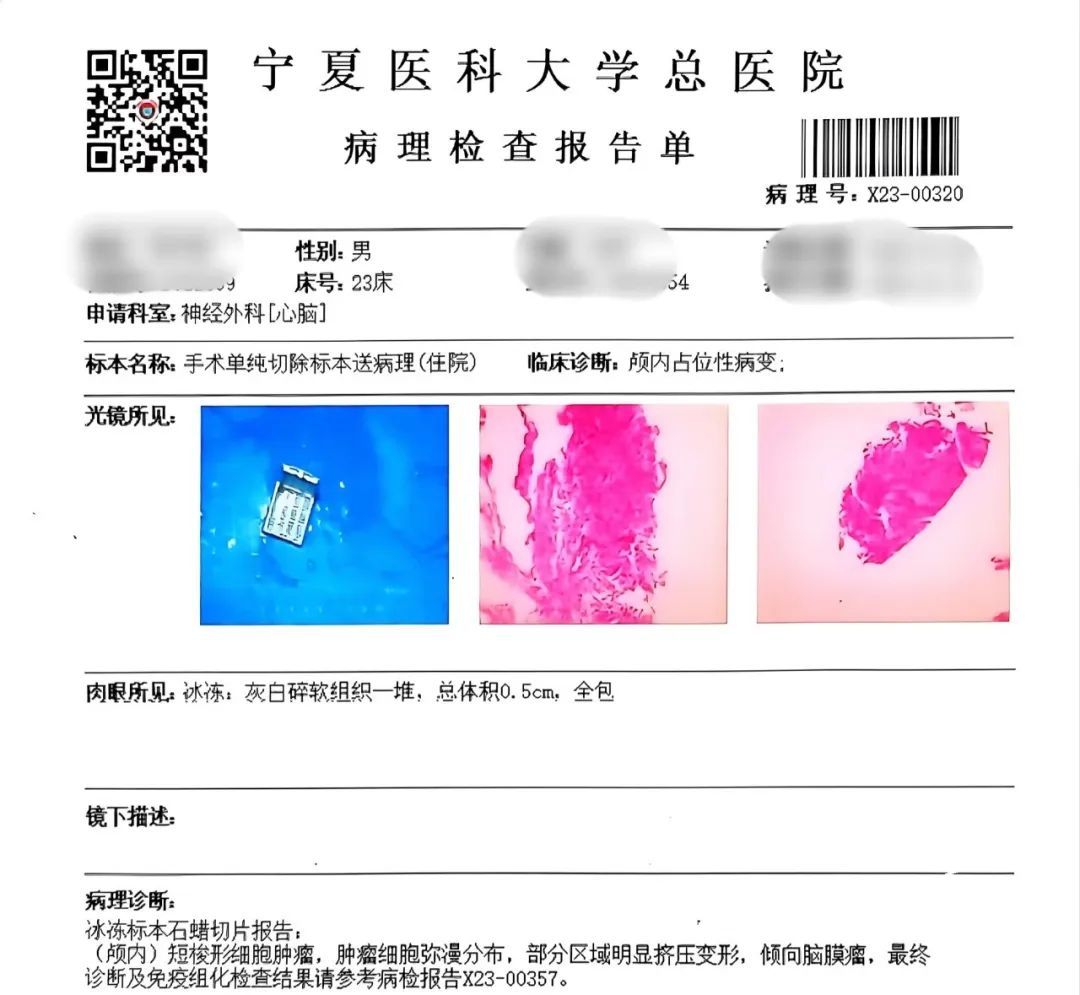

术后病理标本示:倾向(颅内)脑膜瘤